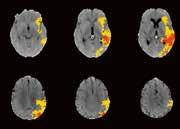

jedes einzelne Pixel. Die Software stellt sogar selbstständig fest, ob die Untersuchung mit oder ohne Kontrastmittel durchgeführt wurde.“ Handelt es sich um eine Untersuchung ohne Kontrastmittel, sucht Auto-Stroke nach einer Gehirnblutung und erkennt selbstständig die unterschiedlichen Arten: subdural, epidural oder subarachnoidal. Wurde bei der Untersuchung Kontrastmittel verwendet, sucht die Maschine nach einem Gefäßverschluss. Und auch Perfusionsstudien werden automatisiert ausgewertet. Sowohl die ausgewerteten Bilder als auch die maschinell erstellten Reports werden direkt ins PACS geschickt. Man kann das System auch so einstellen, dass es den Report per E-Mail entweder an die behandelnden Ärzt*innen oder zusätzlich an die Radiolog*innen versendet. Im PDF-

Befundbericht sind in den Bildern die verdächtigen Areale markiert beziehungsweise farblich hervorgehoben, so dass leicht zu erkennen ist, wo eine Veränderung stattgefunden hat.

Hohe Sensitivität und Spezifität

Trotz der enormen Verlässlichkeit des Algorithmus liegt es an den weiterbehandelnden Ärzt*innen, das automatisiert erstellte Ergebnis zu validieren. Für die Analyse intrakranieller Blutungen wurde der Deep-LearningAlgorithmus anhand von mehr als 10.000 Fällen trainiert. Die gemessene Sensitivität beträgt 92 Prozent und die Spezifität erreicht einen Wert von 97,5 Prozent. Bei der Unterscheidung von Gefäßverschlüssen liegen die Werte von Sensitivität und Spezifität

bei jeweils 98 Prozent. Bei der CT-Perfusionsmessung nutzt die Anwendung die Bayesischen CTP+-Algorithmen, um die Penumbra und den Infarktkern ohne einen einzigen Klick zu quantifizieren. Dabei können nicht nur 2D-, sondern auch 4D-Studien gleichermaßen ausgewertet werden. Der große Vorteil von Auto-Stroke besteht darin, dass die Kliniker*innen innerhalb kürzester Zeit einen kompletten Befundbericht zugeschickt bekommen, um schnell die richtige Therapie-Entscheidung treffen zu können. Das System ist in der Lage, innerhalb eines Zeitraums von etwa 30 bis maximal 60 Sekunden automatisiert und mit hoher Zuverlässigkeit Schädel-CT-Scans auszuwerten und unterschiedliche Arten von Schlaganfällen zu differenzieren. //

Automatisierte Befundberichte

▪ Für intrakranielle Blutungen

▪ Unterstützt die Erkennung mehrerer Varianten von Blutungen

▪ Benachrichtigt den Benutzer über das Vorhandensein einer DICOMBildausgabe, die das Vorhandensein einer potenziellen Blutung hervorhebt, und zeigt verdächtige Schichten an

Große Gefäßverschlüsse

▪ Liefert DICOM-Bilder, die das Vorhandensein einer potenziellen LVO in der M1- und M2-Region hervorheben

▪ Weist den Anwender auf das vermutete Vorhandensein einer LVO hin und zeigt die potenzielle Position und die vermuteten Schichten an, in denen die LVO sichtbar gemacht werden kann

▪ Automatische Ausgabe von fünf parametrischen Karten: Zeit bis zum Maximum (Tmax), mittlere Transitzeit (MTT), relativer zerebraler Blutfluss (rCBF), relatives zerebrales Blutvolumen (rCBV) und Zeit bis zum Maximum (TTP)

▪ Übersichtskarten kommunizieren die Ergebnisse einer CT-Perfusionsuntersuchung und liefern eine Gewebeklassifizierung

36 // VISIONS 31

Olea Puls –mit „0“ Klicks in

30 Sekunden zum Report

Canon Medical Systems perfektioniert mit Olea Puls den Workflow in der Neuroradiologie. Die Anwender müssen keinen einzigen Klick tätigen, damit sie einen vollständigen Report bekommen, der essentiell für die weitere Behandlung sein kann.

„Time is Brain.“ Sobald für einen Patienten ein akuter Verdacht auf einen Schlaganfall im Raum steht, läuft bekanntlich die Stoppuhr. Die neurologische Abklärung und eine Hirnperfusionsuntersuchung zur weiteren Diagnostik im CT oder MRT sind binnen weniger Minuten abgeschlossen.

Aufgrund unterschiedlicher Expertisen beim Personal kann die anschließende Nachverarbeitung und Auswertung des Bildmaterials, normalerweise, ebenfalls einige Minuten dauern.

Canon Medical Systems bietet daher die Software Olea Puls an, die vollautomatisch und selbstständig CToder MRT-Perfusionsbilder des Kopfes auswertet, einen Report erstellt und diesen ins PACS einstellt und/oder per E-Mail an den behandelnden Arzt verschickt. Die Erstellung des vollständigen Reports dauert in der Regel ca. 30 Sekunden. Ein sehr wertvoller Zeitgewinn, der dem Patienten zugutekommt.

Der Report enthält bei einer CT-Hirnperfusion Angaben zu rBF, rBV, MTT, TTP, TMAX, tMIP.

Bei einer MRT-Hirnperfusion enthält der Report Angaben zu B1000, ADC, rBF, rBV, MTT, TTP, TMAX.

Unterschiedliche Color-Maps mit eindeutigen Infarktzeichen der linken Hirnhälfte.

https://de.medical.canon

Eindeutige Visualisierung des Infarktkerns (rot) sowie der Penumbra (gelb). Zusätzlich werden die Volumina, das Mismatch Ratio und das Relative Mismatch dargestellt.

rBV MTT rBF TMAX tMIP TTP